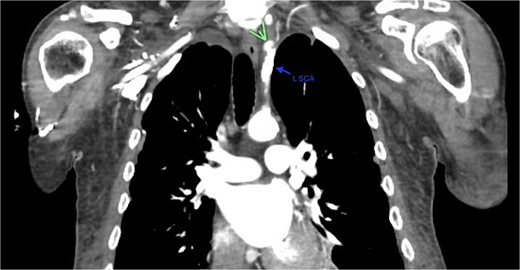

A 67-year-old male with a medical history significant for hypertension, diabetes, coronary artery disease, carotid artery stenosis, osteoarthritis, and 50 pack-year smoking history presented initially to an orthopedic surgery office for evaluation of left shoulder pain after exercising. The patient was found to have an underlying rotator cuff injury and was subsequently treated with cortisone injection. The patient subsequently developed septic arthritis, ultimately requiring incision and drainage of the abscess and resection of the sternoclavicular joint, partial first rib, and partial clavicle. The patient required multiple washouts and debridement procedures, ultimately leading to septic shock and bacteremia requiring close observation in the surgical intensive care unit. A computed tomography angiogram (CTA) of chest was performed at the time and revealed a subcentimeter penetrating ulcer, arising from the proximal left subclavian artery likely secondary to surgical trauma, which was observed nonoperatively given the patient critical status in the intensive care unit (ICU) (Figs 1 and 2). During the ICU course, the patient developed left upper extremity swelling A left upper extremity duplex ultrasound subsequently revealed a nonocclusive deep vein thrombosis of the subclavian vein and also showed resolution of a pseudoaneurysm (PSA) of the subclavian artery. The patient was started on anticoagulation at this time for a deep vein thrombosis (DVT). The patient was ultimately discharged upon resolution of his acute infection to a rehabilitation facility. During the third-month follow-up office visit, the fistulous connection between the subclavian artery and vein was found incidentally on left upper extremity duplex ultrasound (Fig. 3). Physical exam of the patient was otherwise unremarkable with palpable upper extremity pulses and the patient did not appear to have any symptoms related to the fistula including upper extremity swelling or open wounds. The patient was scheduled for an elective repair of the fistula via endovascular stent graft placement. The patient was brought to the operating room, and the radial artery was accessed with a micropuncture device. Radial artery access was our choice to intervene given the location of fistula. When left upper extremity angiography was performed, it revealed a blush of contrast from proximal subclavian artery, revealing a small fistula between subclavian artery and subclavian vein (Fig. 4). Subsequently, a 6 × 29 mm balloon-mounted stent graft was used to cover the fistula. Completion angiography was performed showing adequate seal with resolution of the fistula (Fig. 5). The patient tolerated the procedure well and was subsequently discharged from the hospital the same day. He was started on antiplatelet therapy post-operatively and continued oral anticoagulation for the DVT. The patient was seen in the office at 3-month follow-up, where a repeat duplex ultrasound revealed normal waveforms and velocities throughout the left arm. He was also seen in the office recently, and he is doing well with no new complaints.

Demonstration of pseudoaneurysm of the proximal left subclavian artery on axial image (green arrow: L SCA PSA, blue arrow: left subclavian artery, yellow arrow: left common carotid artery).

Demonstration of pseudoaneurysm of the proximal left subclavian artery on axial image (green arrow: L SCA PSA, blue arrow: left subclavian artery).